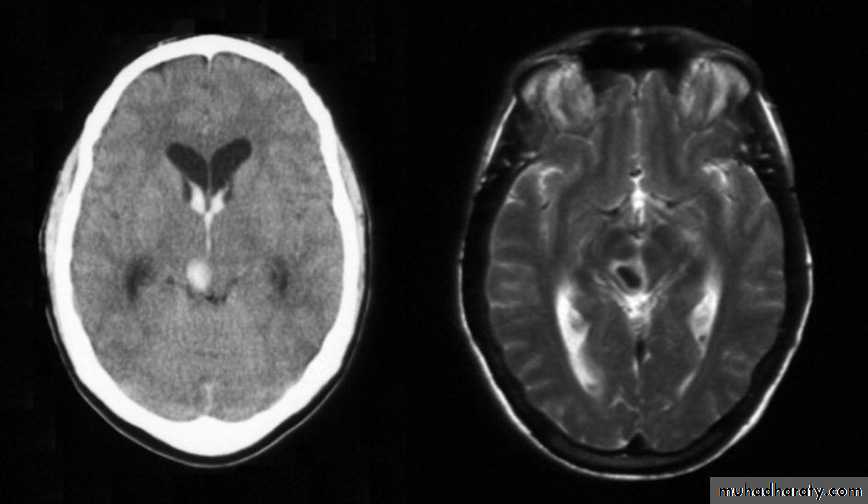

III- Brain edema:

A frequent complication of head injury: it is an expansion of the extra vascular fluid compartment in the brain. The edema usually reaches its maximum limit after 48 hours.Bram edema can lead to increased intracranial pressure. Increased intracranial pressure can lead to Ischemia and the decreased blood supply to the brain leads to more edema due to congestion. So there will be a vicious circle until there's shooting of intracranial pressure and this will lead to cerebral herniation as an attempt to compact the increased intracranial pressure, herniation can cause serious reduction in the blood supply of the brain.

Normal brain oedematous brain

Diagnosis:Clinically by deterioration of the general condition.

CT scan will show decrease in the size of the ventricles because when

there's edema it will press the brain and lead to decrease in the ventricles

size, also there will be decrease in the density of brain tissue (the color of the

brain tissue will be slightly lighter), but these findings are usually not

significant

Diagnosis is not easy because the ventricles are already small in size, so it is almost diagnosed by exclusion of hematoma or other causes.